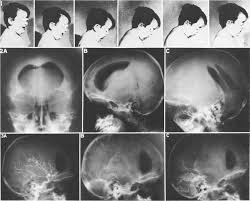

hoi_chung_dau_bup_be1.jpg

Hình chụp cắt lớp não bộ

của bệnh nhi bị hội chứng đầu búp bê.

Bác sĩ sẽ chỉ định cho làm một số xét nghiệm như chụp cắt lớp hoặc

chụp cộng hưởng từ não bộ nhằm tìm ra nguyên nhân chính xác và định vị trí tổn

thương. Từ đó, bác sĩ sẽ có phương pháp điều trị thích hợp nhất. Dự kiến thời